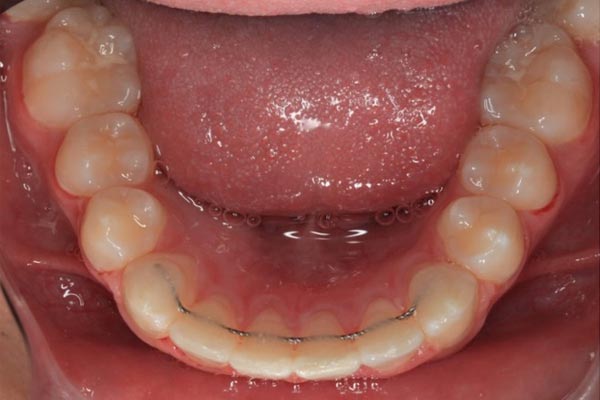

Bonded wire and removable retainer.

A bonded semi-permanent wire is bonded to the insider of your upper and/or lower teeth. It requires more maintenance in cleaning and long-term as it may need to be repaired. Think of it like your insurance policy, if you forget or lose your retainer, the front teeth won’t move out of place quickly. These wires are only offered if you have had great oral hygiene throughout treatment. If you have a bonded wire, we will ask you to wear your clear retainer approximately 12 hours a day.